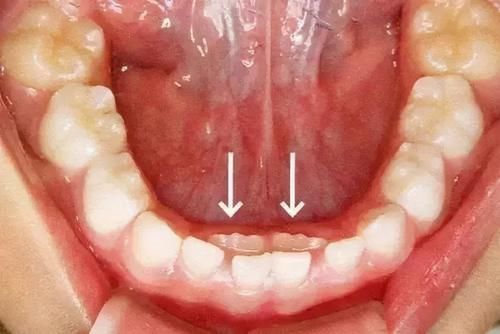

要时刻注意孩子的牙齿发育,及时的解决异常情况。有时候,一些看似影响并不是很大的问题,极有可能会因为时间的推移而变成大问题。就

比如:牙齿稀松、生长位不正、牙病、牙齿间距大等等。这些并不一定是“天生”的,可能是因为某些可变原因造成的。

所以,一旦发现孩子的牙齿出现异常,及时的就医检查,获取最佳的治疗方案,才是最重要的。